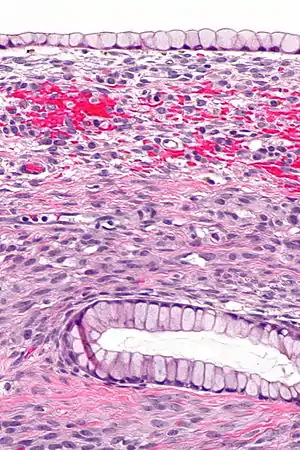

| Germ cell tumor | Mature teratoma of the ovary[9] | 20% of all ovarian tumors[9] | Mostly benign, rarely become cancerous[9] | Cystic, with elements of all 3 germ layers (endoderm, mesoderm and ectoderm).[10] | ![]() Hair follicles. | ![]() |

| Immature teratoma of the ovary[11] | 2.5% | 100% | A teratoma that contains anaplastic immature elements, and is often synonymous with malignant teratoma.[12] | ![]() | ||